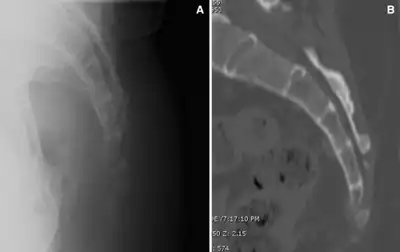

Fractured coccyx in a individual who was diagnosed with coccydynia

A number of different conditions can cause pain in the general area of the coccyx, but not all involve the coccyx and the muscles attached to it. The first task of diagnosis is to determine whether the pain is related to the coccyx. Physical rectal examination, high resolution x-rays and MRI scans can rule out various causes unrelated to the coccyx, such as Tarlov cysts and pain referred from higher up the spine. Note that, contrary to most anatomical textbooks, most coccyxes consist of several segments: 'fractured coccyx' is often diagnosed when the coccyx is in fact normal or just dislocated at an intercoccygeal joint.[6][7]

Sagittal view of coccyx in standing and sitting position

Sagittal coccygeal movement is measured using the angle of incidence—or the angle at which the coccyx strikes the seat when an individual sits down.[10] A smaller angle indicates the coccyx being more parallel to the seat, resulting in flexion (or “normal” movement) of the coccyx.[10] A larger angle indicates the coccyx being more perpendicular to the seat, causing posterior subluxation (or “backward” movement) of the coccyx.[10]